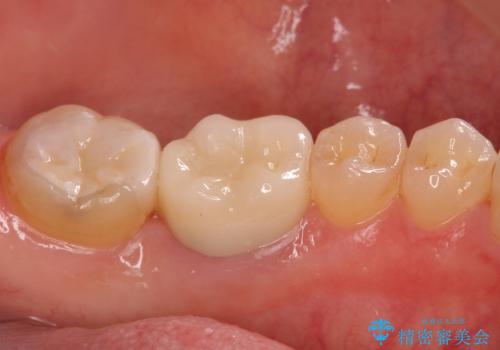

セラミックでの治療をご希望されましたが、残っている歯が少なかったためクラウンでの治療を行いました。

- 右下6:仮歯+セラミッククラウン/11,000円+110,000円 右下7:セラミックインレー/77,000円費用は治療当時の料金となります

残る歯が薄かったり、十分な量を確保できない場合はクラウンで治療した方が今後の破折リスクを抑えることができます。